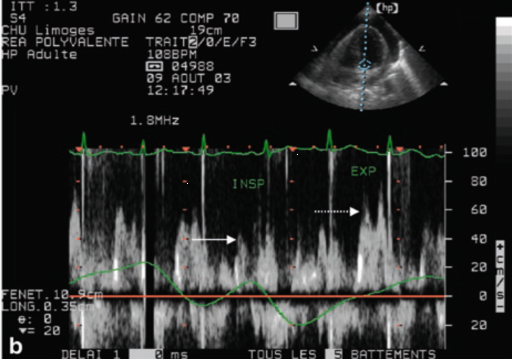

通过组织多普勒频谱分析也可以识别心包压塞。因为在生理状态下,左心室每搏量(SV)在吸气相轻微下降、呼气相轻微增加,右心室SV与之相反。正常情况下SV在吸气-呼气相差异较小;如果SV差异性增大,则提示心包压塞。在心包压塞的患者中,二尖瓣/三尖瓣流速在吸气相与呼气相差异度增大,表现为二尖瓣E波峰值流速在吸气时下降率≥25%;而跨三尖瓣流速增加≥40%。

如图10和图11所示:基于二尖瓣及三尖瓣血流频谱分析心包压塞的血流动力学特征:①二尖瓣血流频谱(图10):呼气相二尖瓣峰值流速约60 cm/s,吸气相降至约40 cm/s。二尖瓣峰值速度变异率=(60-40)/60×100%≈33%。当二尖瓣血流呼吸变异率>25%时,提示存在心包压塞。②三尖瓣血流频谱(图11):吸气相三尖瓣峰值流速约为80 cm/s,呼气相约为40 cm/s。三尖瓣峰值流速变异率=(80-40)/80×100%=50%。当三尖瓣流速增加≥40%,提示存在心包压塞。

图片

10  二尖瓣血流频谱

11  三尖瓣血流频谱